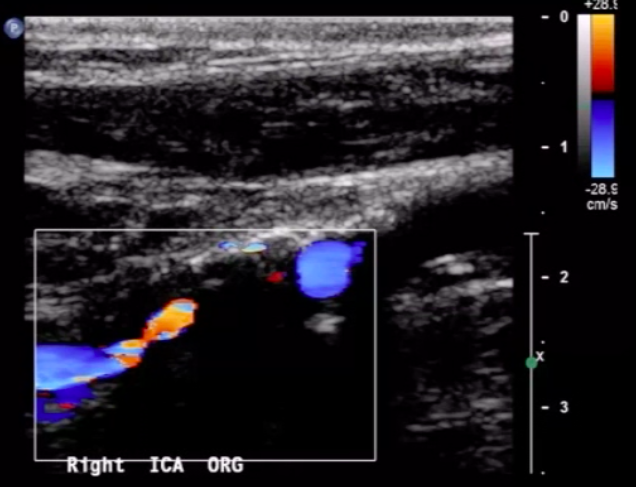

For the following arterial duplex US (DUS) image:

comment on the PRF setting

PRF is set very low

you can tell this based on the velocity range of the color bar (range of 12 cm/s, relatively low setting

recall that PRF value is directly-related to color doppler frequency parameters (and the associated blood velocity)